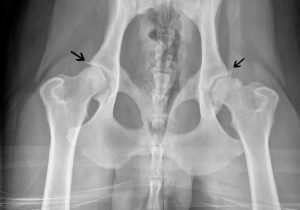

WARNING: Vaccinated dogs developed auto-antibodies to their own collagen HIP DYSPLASA IN DOGS